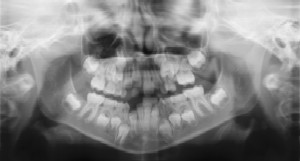

Radiographs (X-Rays)

Radiographs (X-Rays) are a vital and necessary part of your child’s

dental diagnostic process. Without them, certain dental conditions can and

will be missed.

Radiographs detect much more than cavities. For example, radiographs may be

needed to survey erupting teeth, diagnose bone diseases, evaluate the

results of an injury, or plan orthodontic treatment. Radiographs allow dentists

to diagnose and treat health conditions that cannot be detected during a

clinical examination. If dental problems are found and treated early, dental

care is more comfortable for your child and more affordable for you.

The American Academy of Pediatric Dentistry recommends radiographs and examinations every six months for children with a high risk of tooth decay.

On average, most pediatric dentists request radiographs approximately once a

year. Approximately every 3 years it is a good idea to obtain a complete set

of radiographs, either a panoramic and bitewings or periapicals and

bitewings.

Pediatric dentists are particularly careful to minimize the exposure of

their patients to radiation. With contemporary safeguards, the amount of

radiation received in a dental X-ray examination is extremely small. The

risk is negligible. In fact, the dental radiographs represent a far smaller risk

than an undetected and untreated dental problem. Lead body aprons and

shields will protect your child. Today’s equipment filters out unnecessary

x-rays and restricts the x-ray beam to the area of interest. High-speed film

and proper shielding assure that your child receives a minimal amount of

radiation exposure.